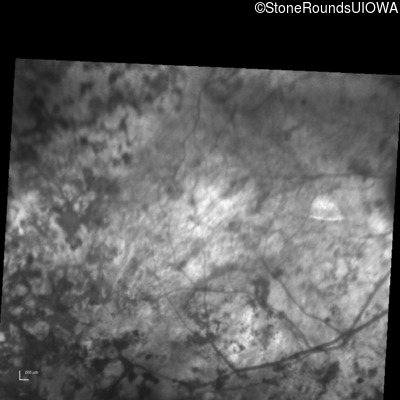

Infrared Fundus Photograph - Left - Light Perception

Exemplar